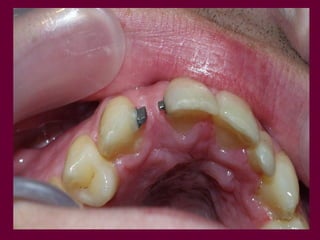

Conocer los diversos recursosprotéticos que dispone la odontología Prótesis fija Prótesis removible parcial Prótesis removible total Prótesis implanto-asistida

SOPORTE es lapropiedad de la prótesis de trasmitir a los tejidos (mucosa-hueso y sistema periodontal) los esfuerzos funcionales sin alteraciones patológicas. Depende de los propios tejidos y de la prótesis en si misma